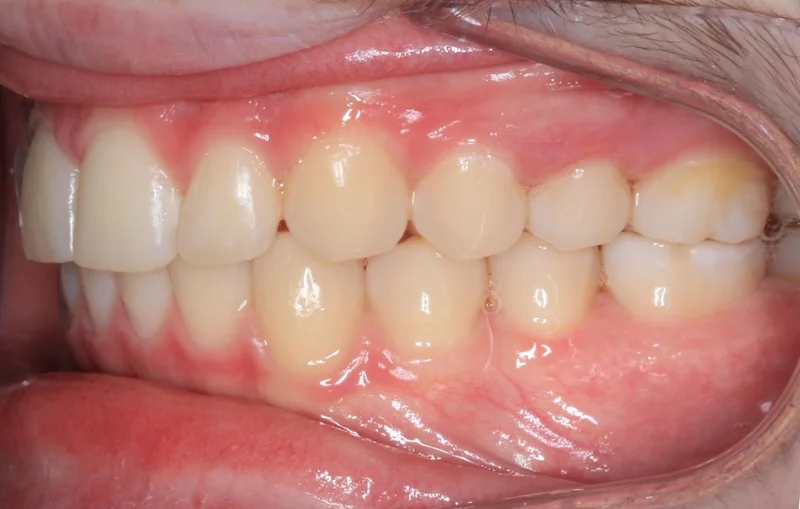

Left Side Bite

Left Side Bite - Before Treatment

Before

Left Side Bite - After Treatment

After